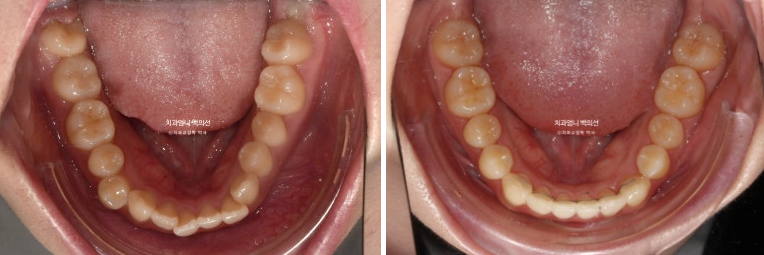

23.07~25.04

배열은 좋고

결손치 쪽으로 돌아가있던 상악 중심선은 아래중심선과도 만나게 되었습니다.

뻗쳐있던 앞니 각도가 개선이되고 입매가 정돈되었습니다.

발치했으면 큰일날뻔 했죠

앞니 뻗침도 개선이 되었습니다.